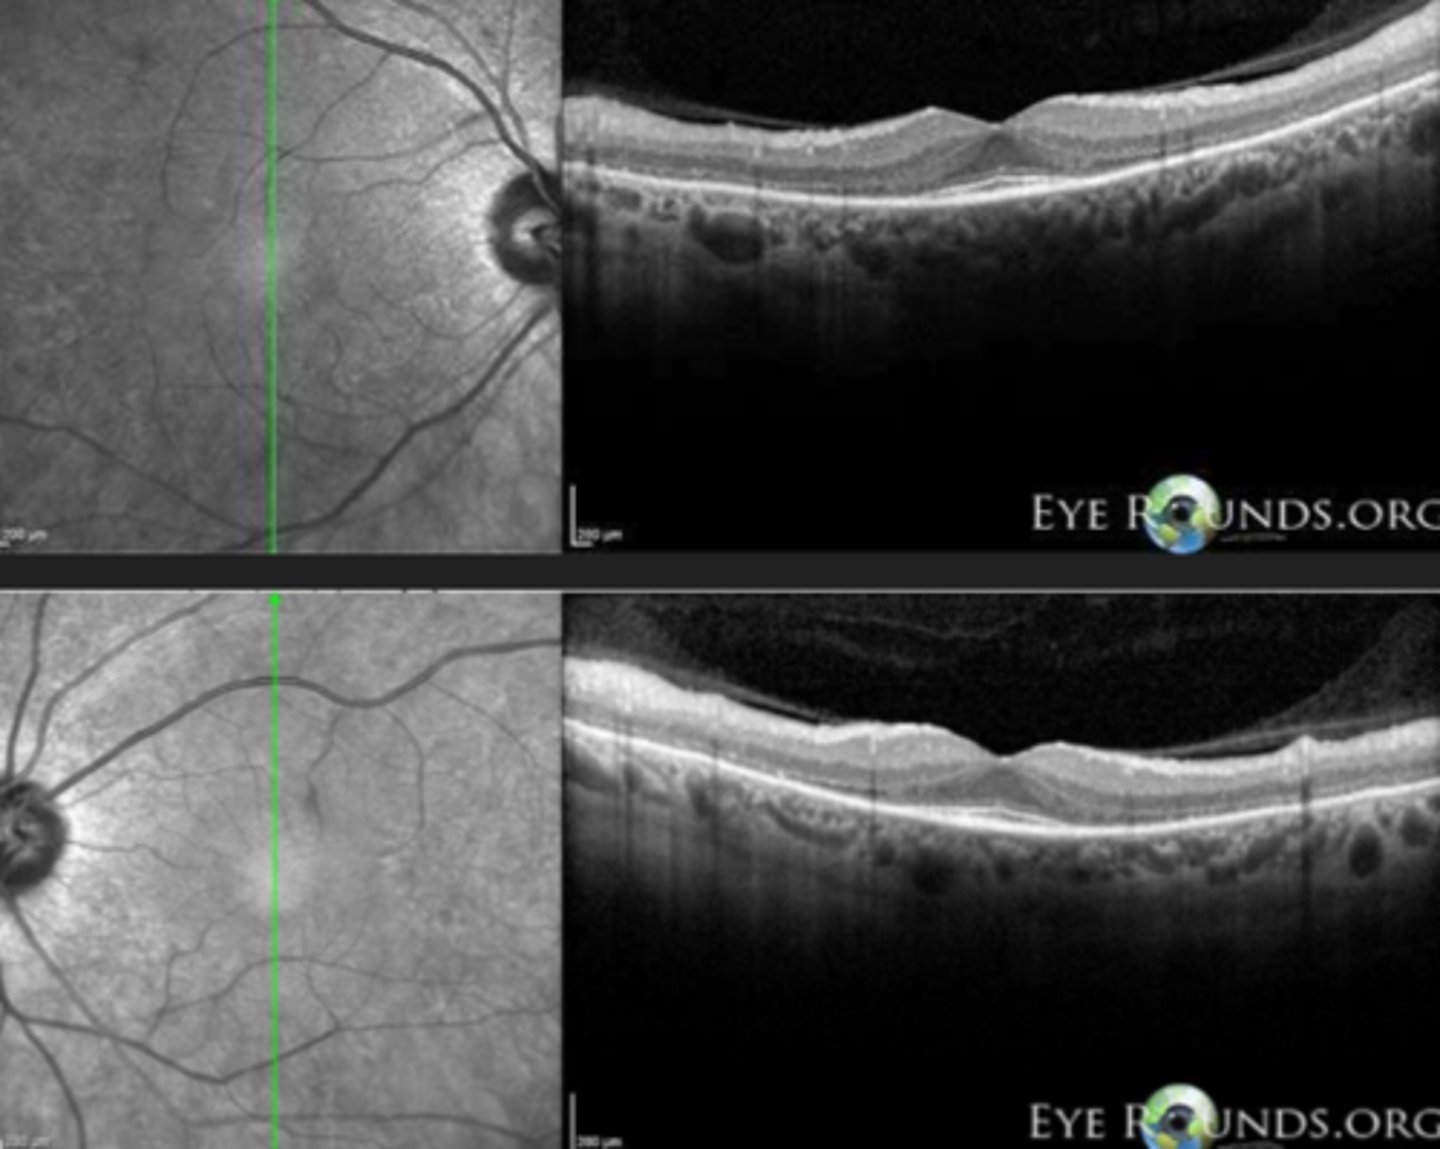

What feature of RP sine pigmento is seen here?

perifoveal loss of PR's and RPE on OCT = ring scotoma very close to fixation seen on HVF

What feature of sectoral RP is seen here?

still has PIL loss and RPE thinning on OCT